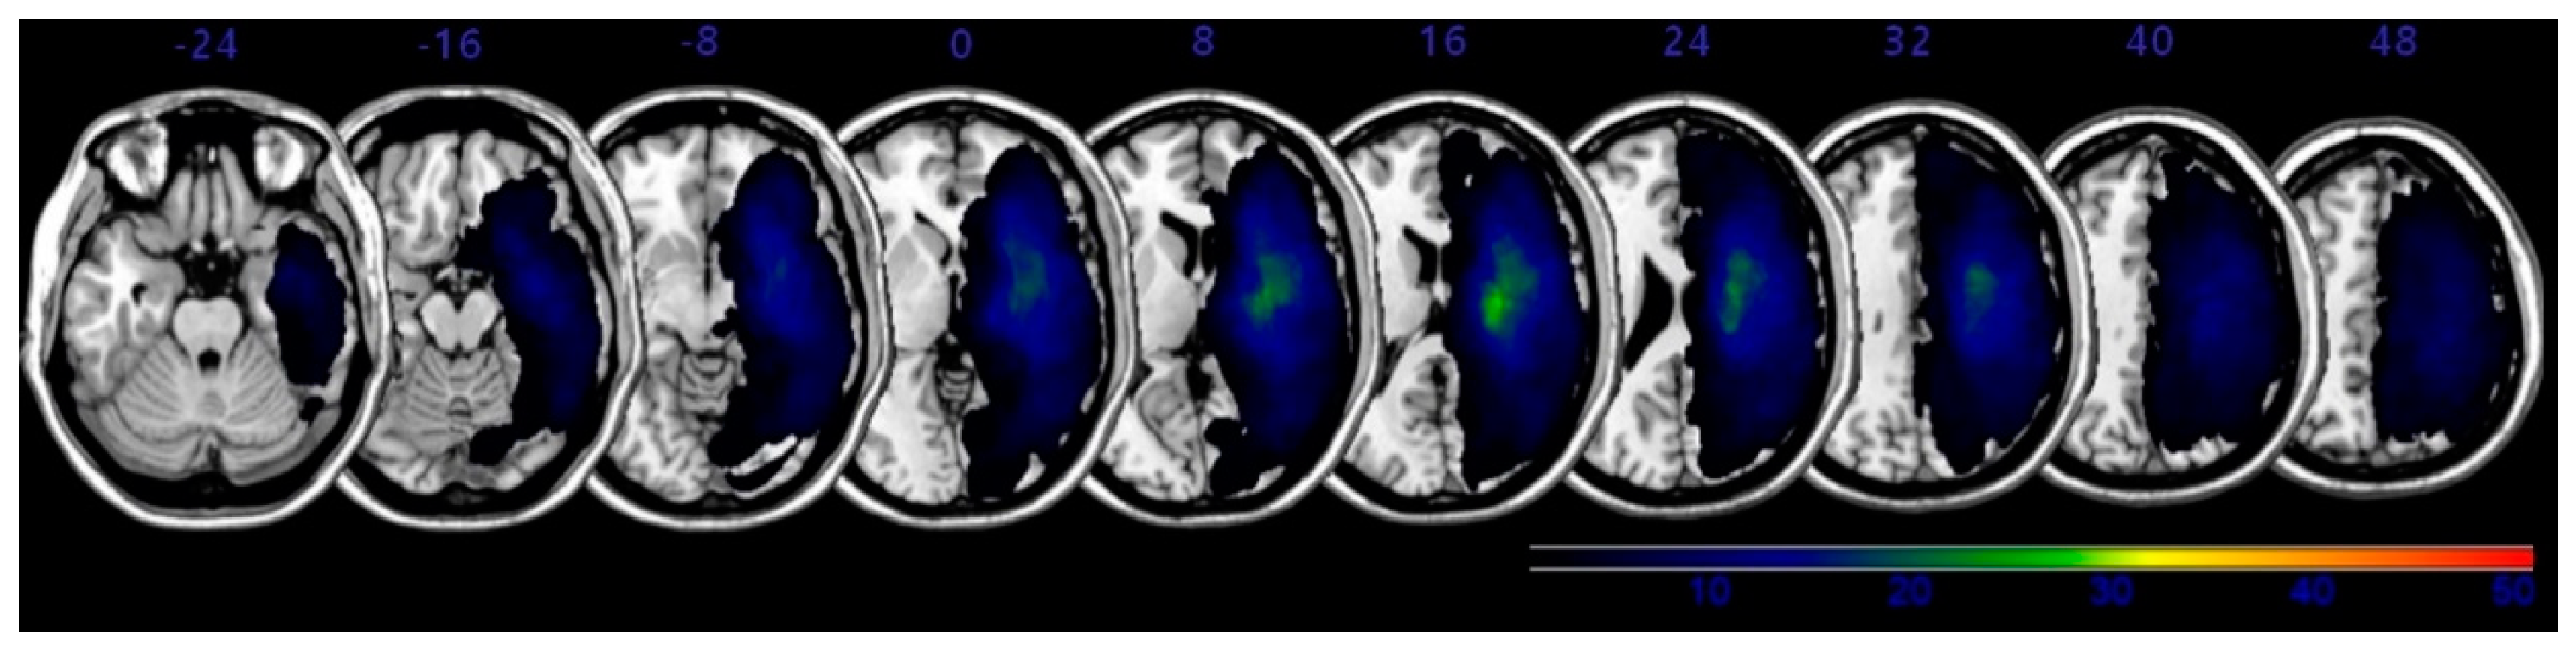

The overlapping lesions in the brains of all stroke patients were created on a standard MNI space brain. (Figure 1; the color represents the frequency of overlap). The VLSM method with SnPM (statistical non-parametric mapping) demonstrated the region that corresponded to SCP (Figure 2 and Table 3). Before adjusting the lesion volume, the precentral gyrus, postcentral gyrus, inferior frontal gyrus, insula and subgyral parietal lobe of the right hemisphere were noted for producing the lateropulsion. However, after adjusting the lesion volume as nuisance covariates, no statistically defined lesion areas were associated with SCP scores in Table 3.

Figure 2. Voxel-based lesion symptom mapping (VLSM) was combined with statistical non-parametric mapping (SnPM) to associations of lesion areas with Scale for Contraversive Pushing (SCP) scores. Lesion overlay map in Montreal Neurologic Institute (MNI) space for SCP scores. Only voxels significant at p < 0.05 (familywise error correction) are shown in red to yellow color. Numbers are the z-coordinates in MNI space; the patient’s right hemisphere is on the right side of the figure. After adjusting for lesion volume as a nuisance covariate, no lesion areas were definitively associated with SCP.